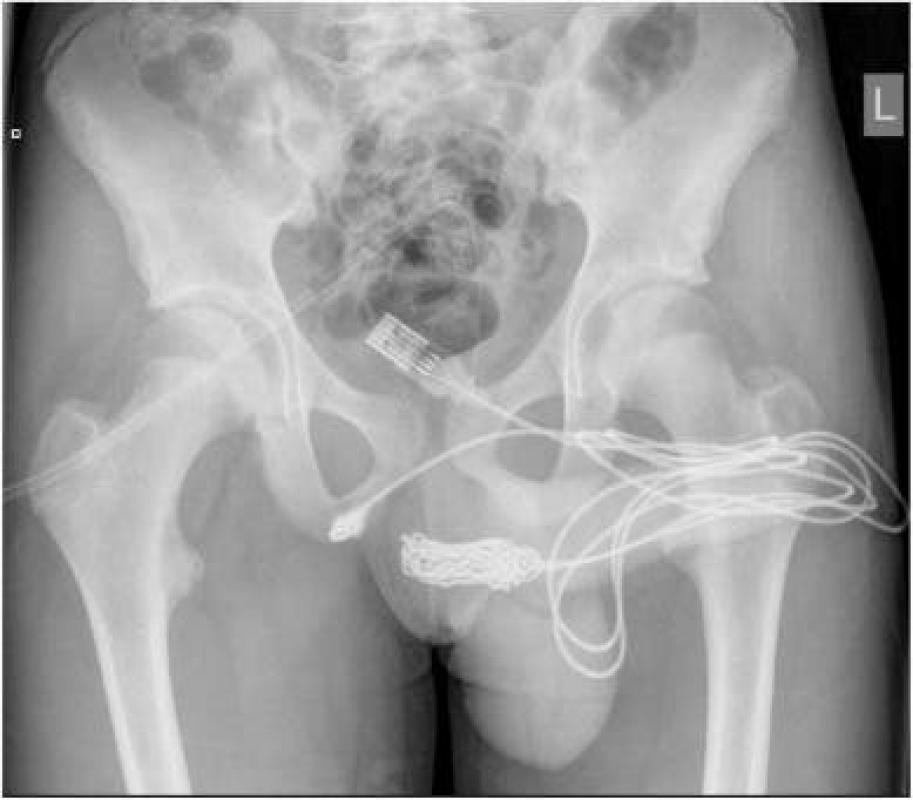

Tras escuchar su testimonio, se le realizó una radiografía pélvica simple, la que dejó al descubierto la posición exacta del cable -que se había enredado- en el interior de su uretra.

Joven de 15 años tuvo un cable de USB atrapado en la uretra: Quería medir su pene